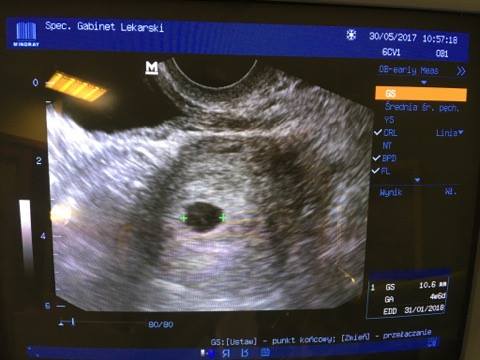

ok już wysyłam oba zdjęcia

18815994_1405253059514189_715976382_n.jpg

• 18815994_1405253059514189_715976382_n.jpg

24,8 KB · Wyświetleń: 506

Przyszłamama z tego pierwszego to chyba faktycznie za szybko bo nie ma tak typowo jasnego miejsca.